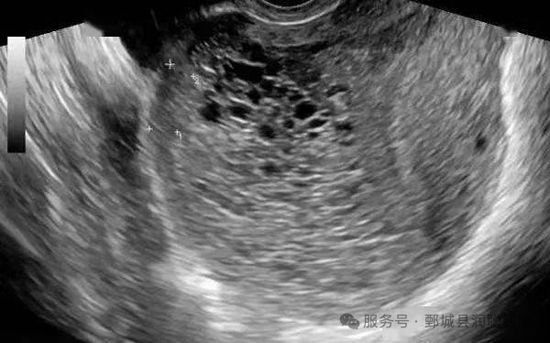

完全性葡萄胎的典型B超表现:

(1)子宫明显大于相应孕周。

(2)无妊娠囊或胎心搏动。

(3)宫腔内充满不均质"落雪状"或"蜂窝状"回声"。

部分性葡萄胎可在胎盘部位出现由局灶性水泡样胎块引起的超声图像改变,有时还可见胎儿或羊膜腔,胎儿通常畸形。

诊疗经过:张女士停经30天自测尿妊娠试验阳性,2天前无明显诱因出现阴道流血情况,量少,色暗。为进一步治 疗,遂来院就诊。彩超检查示:宫腔内未见明显妊娠组织,可见不均质蜂窝状无回声及液性回声。血HCG示:46146mIU/mL。考虑葡萄胎,立即给予其行清宫术,术后送病理。病理示:(宫腔内容物)查见退变的胎盘绒毛及蜕膜组织,局灶胎盘绒毛水肿,似见中 央水池形成,滋养叶细胞增生。免疫组化结果符合完全性水泡状胎块。符合完全性葡萄胎诊断,嘱其避孕套严格避孕及连续4周复查血HCG,每周1次监测血HCG值变化。患者自行当地卫生室复查血HCG值,血HCG值下降理想。第4周本院复查血HCG示:2mIU/mL,彩超示:内膜B形表现,全层厚约10.7mm,内回声不均。后嘱其继续连续监测6个月血HCG值,每月1次。再继续连续监测6个月血HCG值,每2月1次。回访患者后续检测血HCG值均正常。入院彩超检查示: